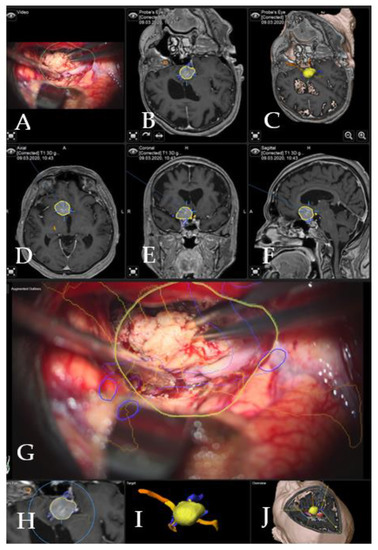

Figure 4. Navigation and AR support following complete resection of the tumor (patient no. 20). (A) Microscope video with head-up display and 3-dimensional (3D) visualization of the segmented objects (tumor in yellow, carotid and anterior cerebral arteries in blue, optic chiasm in yellow). (B,C) Probe’s eye view in 2-dimensional and 3D fashion. (D) Axial, (E) coronal and (F) sagittal views of standard navigation display with the segmented objects (focus on the sellar floor following complete resection). (G) AR display on video screen with the 3D outline of segmented structures. (H) Corresponding probe’s eye view. (I) Target view and (J) overview depicting the video plane in relation to the segmented 3D objects.

Case 2: A 38-year-old female patient with giant medial sphenoid wing meningioma on the left side presented with vertigo (patient number 9). GTR was performed using iCT-based navigation registration and microscope-based AR. Figure 5 demonstrates the intraoperative view throughout the resection and Figure 6 shows preoperative and postoperative MRI imaging. The patient recovered fully and had no neurological deficits. Operative video has been added to the Supplemental Materials: Patient number 9.

Case 3: A 67-year-old female patient (patient number 19) with visual deterioration and bitemporal hemianopsia. MRI showed a suprasellar meningioma which was resected via right pterional approach. Figure 7 demonstrates the visualization of the structures in the AR throughout the surgery.